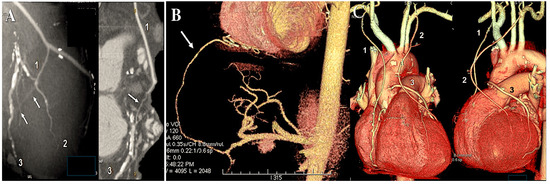

Figure 6.

The illustration depicts the 20-year angiographic control of the radial artery as a secondary conduit on the right coronary artery (RCA), demonstrating the presence of a stenosis at the distal anastomosis. Panels (A–C) illustrate the balloon dilatation of the radial artery (RA) without the use of a stent.